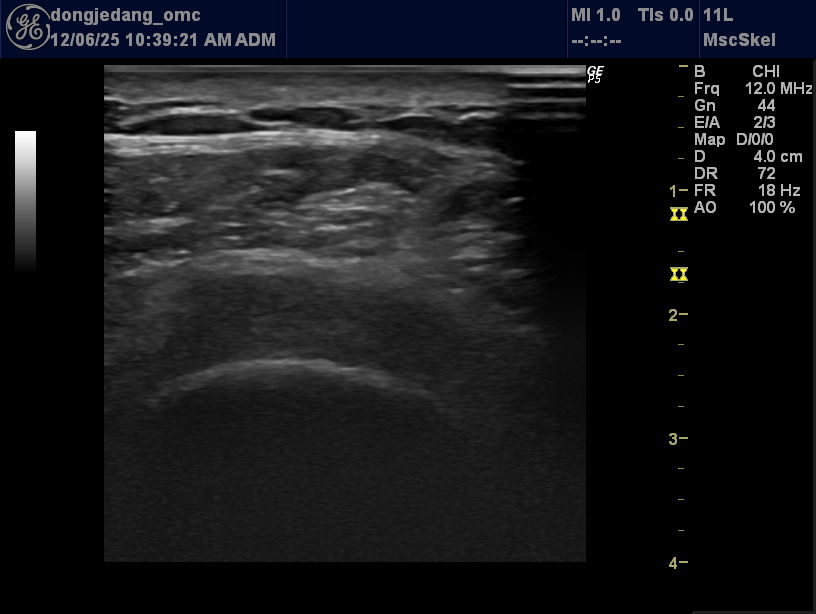

대퇴골 관절면의 경미한 피질 불규칙성(Cortical irregularity) 초자연골(Hyaline cartilage) 두께의 전반적 보존 및 국소적 경계면 모호 뚜렷한 거대 골극(Osteophyte) 형성이나 연골하 낭종(Subchondral cyst) 부재 관절강 내 유의미한 삼출액(Joint effusion) 저류 관찰되지 않음 우슬 초기 퇴행성 관절염(Early Degenerative Osteoarthritis) 소견 임상적 중증도 분류(Kellgren-Lawrence Grade) 추정 시 Grade 1 (미세한 골극 형성 가능성 및 관절 간격의 변화가 의심되나 확정적이지 않은 상태)에 해당할 가능성이 높음. 46세 남성임을 고려할 때 연령 증가에 따른 자연스러운 초기 변화와 병적 변화의 경계선상에 있는 것으로 사료됨.